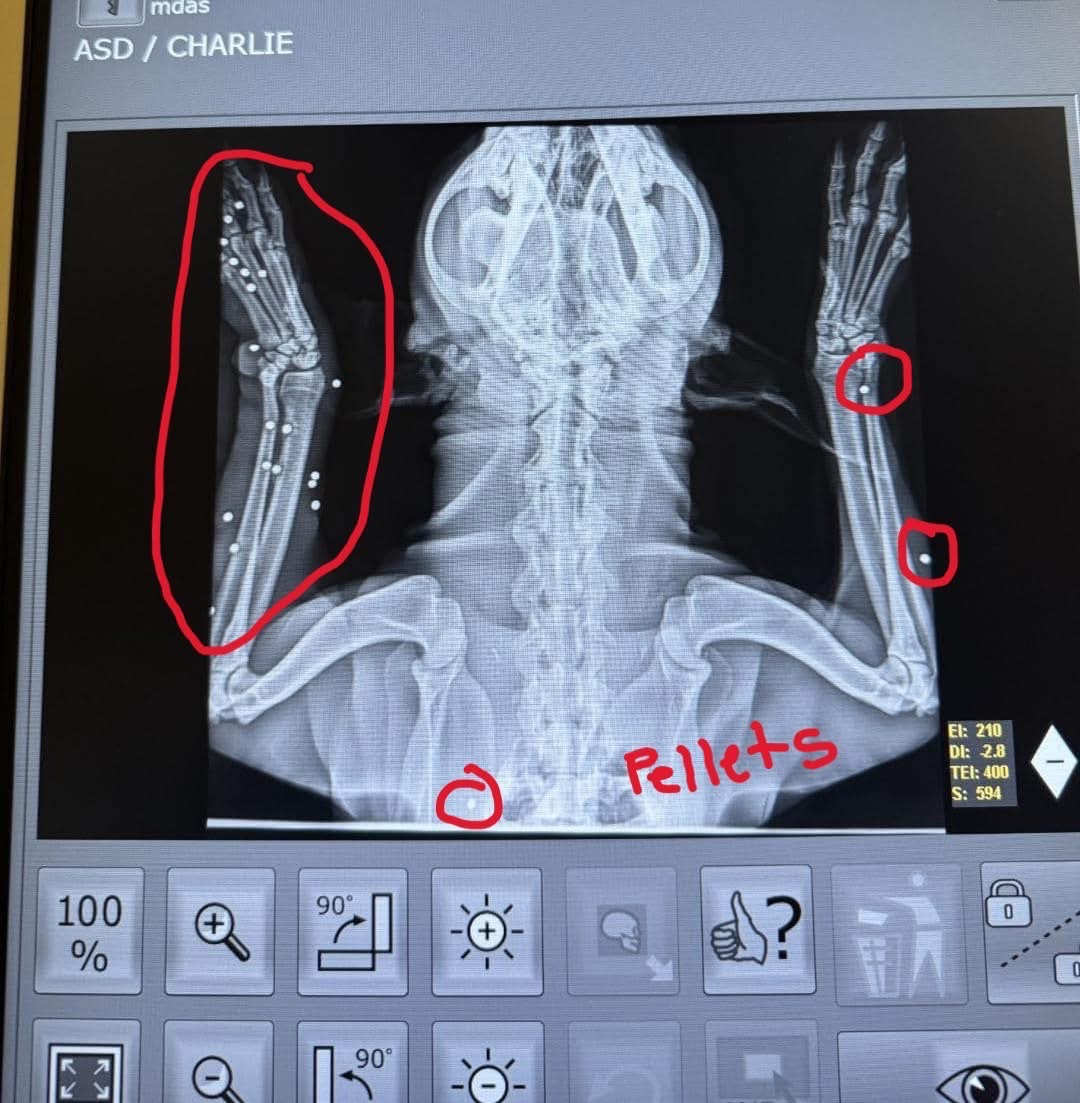

About six months ago, Charlie arrived at Miami Dade Animal Services as a stray. At first glance, he seemed like many other homeless dogs, but a heartbreaking discovery changed everything. Shelter veterinarians found that Charlie had been shot multiple times. Over 20 lead pellets are still lodged in his legs and chest — the result of a cruel and intentional attack by a human.

Charlie’s body is filled with dangerous lead pellets. These can cause lead poisoning, chronic pain, and serious long-term health issues. He urgently needs surgery to remove them but the shelter does not have the resources to provide the care he needs.